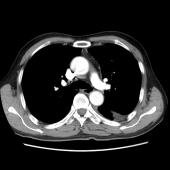

[影像描述]

左肺下叶可见高密度肿块影,边界清晰,边缘不规则,左肺下叶支气管局部截断,增强后病灶边缘轻度强化,中心未见明显强化;左侧胸腔内可见液性密度影;纵隔内未见明确肿大淋巴结影。

(左下叶)肺肉瘤样癌(巨细胞癌),伴大片坏死

肺肉瘤样癌是一种少见的非小细胞肺癌,WHO将其分为5个亚型:多形性癌、梭形细胞癌、具巨细胞癌、癌肉瘤和肺肉瘤。主要见于老年患者,男多于女,临床症状与肿瘤生长部位及侵犯周围组织的情况有关,中央型较易侵犯支气管,症状往往出现较早。CT多表现为肺内单发肿块影,最大径一般大于5cm,周围型多于中央型,可跨叶生长;边缘光滑或清晰;毛刺征及胸膜牵拉症少见;坏死、空腔及分叶、支气管截断多见,坏死边界不清,可见坏死内强化灶,肺门及纵隔淋巴结转移多为环形强化。需要鉴别以下几种疾病:肺结核球呈圆形或类圆形,多数密度不均匀,周边或中央常可见钙化,病灶中心有时可见小空洞。病灶边缘清楚,部分边缘可呈浅分叶状,少数可见毛刺征或胸膜凹陷征,周围常可见卫星灶。增强检查病灶不强化或仅轻度强化。周围型错构瘤直径多在2.5cm以下,瘤体内可见斑点状或爆米花状钙化,部分病变有脂肪密度,多数病变边缘清楚、光滑,CT增强大多数病灶无明显强化。肺炎性假瘤呈圆形或类圆形高密度影,密度较均匀,边缘多清楚而光滑,少数可呈毛刺样改变,增强检查大多数肿块较显著均匀强化。